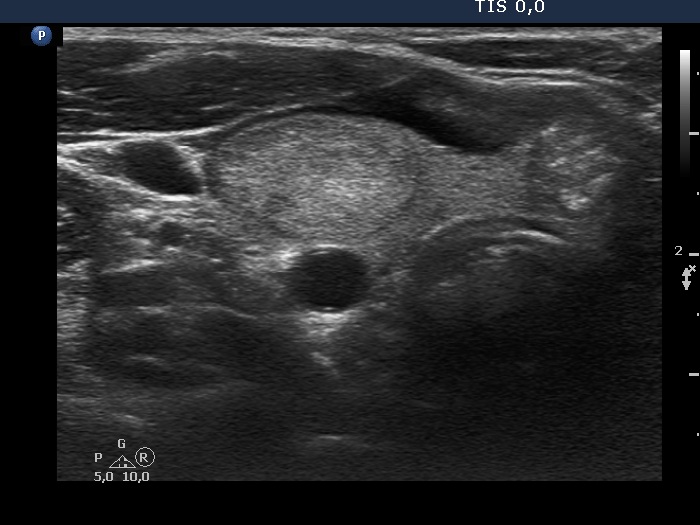

100 consecutive cases of papillary cancer - case 071

Clinical presentation: A 40-year-old woman requested a follow-up. I met her first 11 years ago when a multinodular goiter was found. There was a suspicious nodule in the isthmus with the dimensions of 11x9x14 mm. At that time the patient refused cytology.

Ultrasonography. The thyroid was echonormal. There were two echonormal/hyperechoic nodules in the right lobe. The nodule in the isthmus was hypoechoic, had numerous microcalcifications and showed blurred borders. The dimensions of the lesion were 11x10 13 mm, width x depth x length, respectively.

Cytology resulted in papillary cancer.

Histopathology revealed a T1N0 papillary cancer. The dimensions measured during pathological examination were 10x8x12 mm.